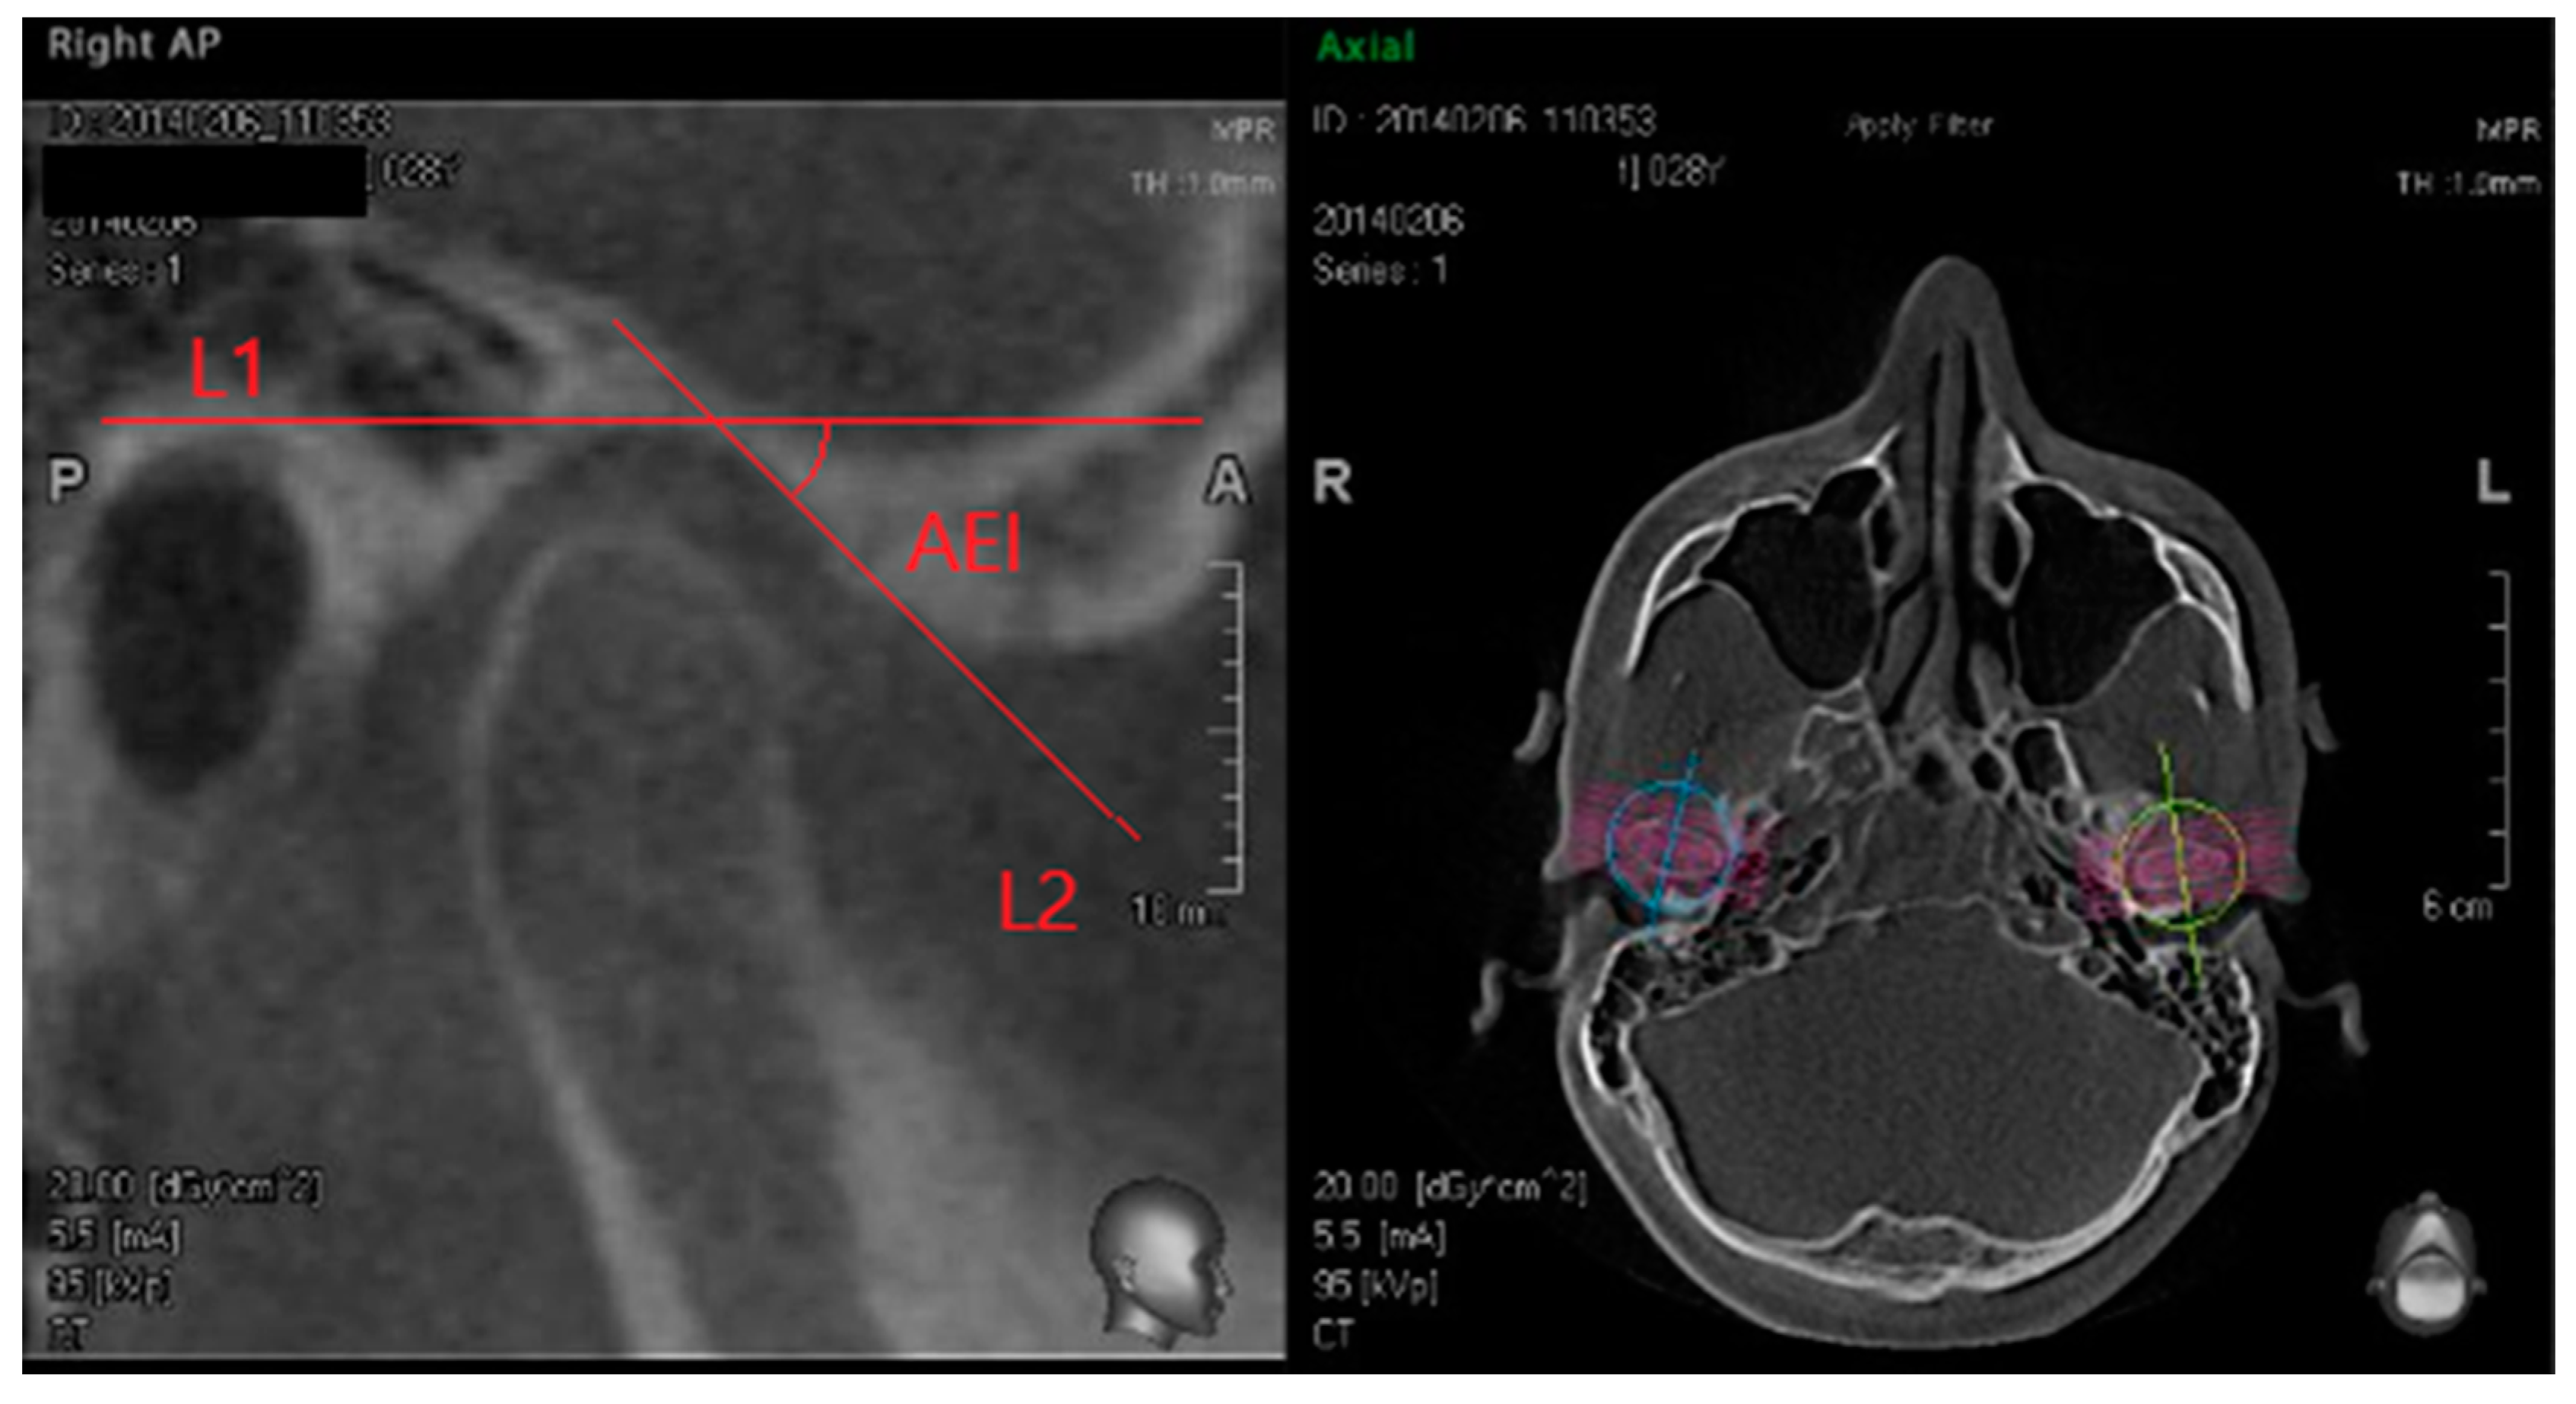

- L1: a first horizontal line, parallel to the Frankfurt plane (FH) passing through the uppermost point of the glenoid fossa.

- L2: a second line, constructed along the posterior slope of articular eminence, connecting the lowermost and most posterior point of the articular eminence and the uppermost and most anterior point of the glenoid fossa on the temporal bone.